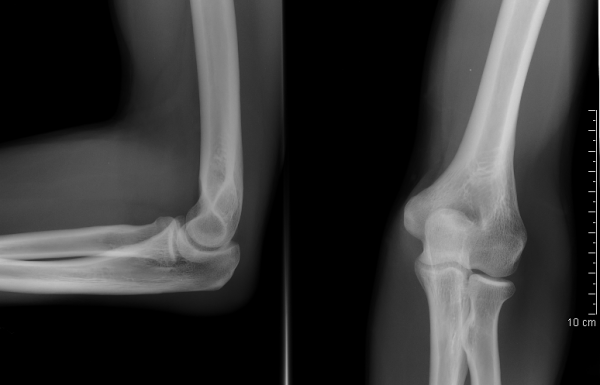

Здоровые локтевые суставы в передне-задней и боковой проекции

- Рентгенография.

- Данные анамнеза по возможности должны коррелировать с результатами рентгенографии.